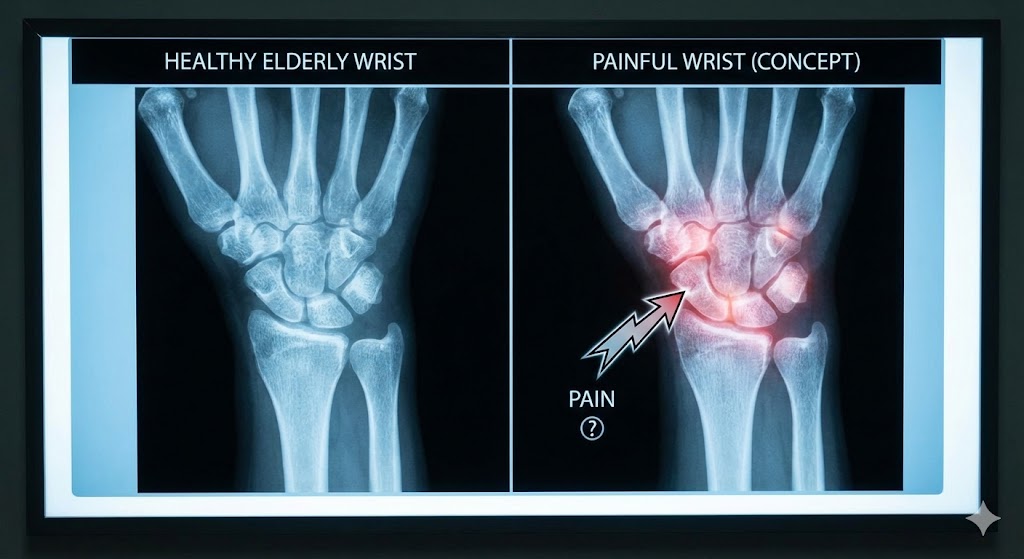

「手首の変形」と「痛み」は無関係!?

まず、あなたの常識を覆す、日本で行われた大規模な研究データ(ROADスタディ)をご紹介します。

70歳以上の日本人を対象とした調査で、ほぼ100%の人に、レントゲン上で「手首や指の変形(骨の変形や軟骨の摩耗)」が見つかりました 。

しかし、その変形を持っている人全員が痛がっているわけではありません。

つまり、「変形があること」は、高齢者にとってはシワや白髪と同じ「当たり前の変化」であり、痛みの直接の原因ではないことが多いのです 。

さらに、MRIを使った調査でも、「手首に痛みが全くない健康な高齢者」の約半数以上に、靭帯(TFCC)の断裂や欠損が見つかっています 。 画像に写っている「傷」や「変形」は、あなたの痛みの犯人ではない可能性が高いのです。